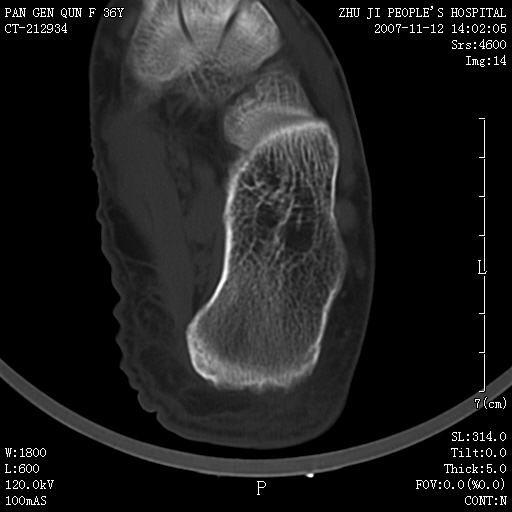

标题: CT10417:F36Y,跟骨跟腱附着处下方骨质密度影,请会诊. [打印本页]

标题: CT10417:F36Y,跟骨跟腱附着处下方骨质密度影,请会诊.

跟骨结节后部肿块半年,无明确外伤史,及红肿热痛.

跟骨骨刺

如果是骨瘤,也应该是骨旁骨瘤。发生部位不支持骨瘤,骨肿瘤提倡临床、放射、病理三结合诊断。